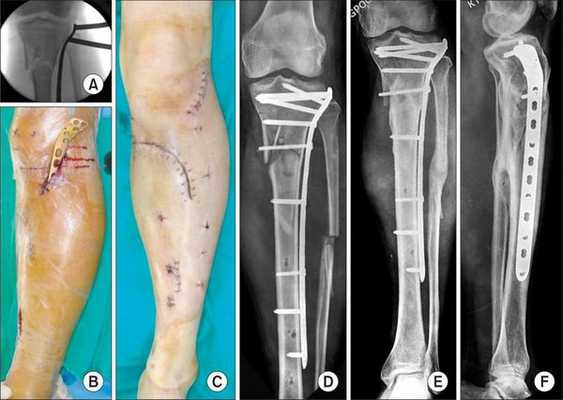

Хирургическое лечение

Хирургическое лечение состоит в открытой репозиции костных фрагментов и остеосинтезе — операции, при которой восстанавливают правильную ось ноги и придают отломкам нужное положение. Процедура проводится под общей анестезией. Подходящую технику остеосинтеза врач подбирает в зависимости от участка перелома.

При использовании металлоконструкций кости голени сращиваются в среднем через 3-3,5 месяца после операции. Удалять конструкции по медицинским показаниям можно не ранее, чем через полгода. К таким показаниям относятся риск перфорации кожи и травмы мягких тканей. Также конструкцию нужно убрать, если она мешает разработке сустава, сдвинулась или поломалась.

Если конструкция мешает пациенту, её можно удалить, но не раньше, чем через год.

Аппараты внешней фиксации, например стержневые фиксаторы или аппарат Илизарова, применяют только временно, пока состояние пациента нестабильно и нельзя провести операцию.

- При обычных свежих повреждениях производят артротомию. Фрагменты, свободно лежащие в полости сустава, удаляют. Крупные отломки вправляют и фиксируют винтом, выполняют интрамедуллярный или накостный остеосинтез гвоздем, спицами или специальными Г- и Т-образными опорными пластинами.

- При многооскольчатых повреждениях большеберцовой кости и открытых переломах осуществляют наружный остеосинтез с использованием аппарата Илизарова.